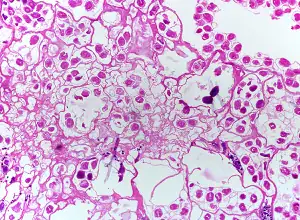

Echinococcus sp. from a liver cyst, stained with Papanicolaou (PAP) stain.